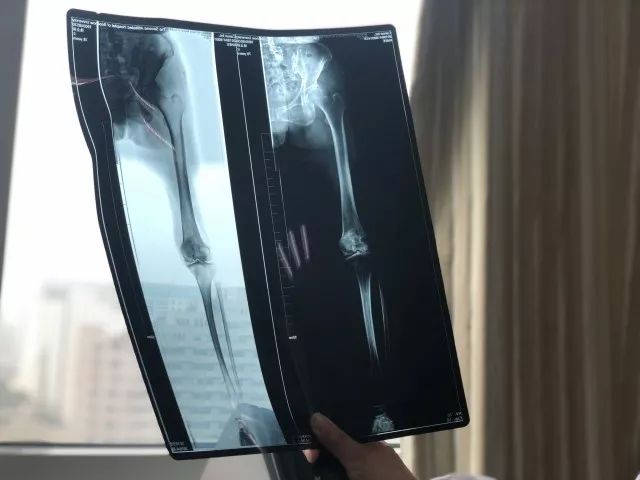

拍的X光片,很模糊,

除非大的骨头断了,看得到,

如果片子有微小的变化,

肉眼很难识别。